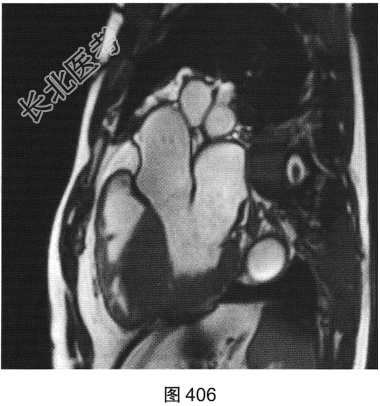

- [材料题] 患者男性,43岁,因“活动后胸痛3年”,外地医院拟诊梗阻性肥厚型心肌病,为明确诊断而转诊本院。

- 简答题3、患者超声心动图检查未能明确诊断,临床申请心脏磁共振检查,如图404~图408所示。患者心脏磁共振检查的异常征象有?